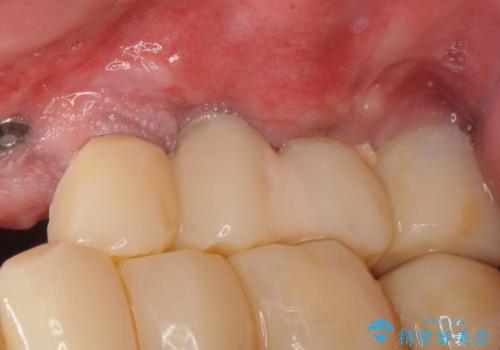

禁煙指導と歯周病治療後、左上臼歯部のソケットリフト(上顎洞底挙上術)及びインプラント治療(左上457埋入)を行いました。

インプラントが長持ちするように、角化歯肉(歯ブラシが当たっても痛くない固くしっかりした歯茎)の移植(遊離歯肉移植術:FGG)も行いました。